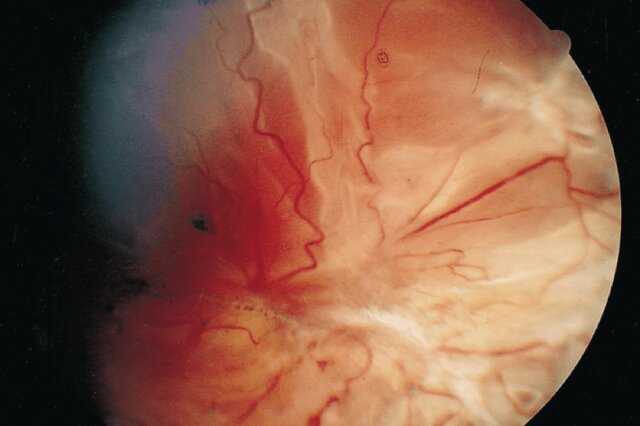

پژوهشگران با کمک این کمکهزینه سه ساله، ایمنی و تاثیر دو پادتن جدید را برای درمان “ویتریورتینوپاتی پرولیفراتیو”(Proliferative vitreoretinopathy) آزمایش خواهند کرد. در حال حاضر، هیچ راهی برای درمان این بیماری یا پیشگیری از آن وجود ندارد. ویتریورتینوپاتی پرولیفراتیو هنگامی رخ میدهد که سلولهای درون چشم پس از آسیب دیدن آن، گردهم میآیند و یک ساختار شبیه به گوی را به وجود میآورند.

سالانه حدود ۲۰۰ هزار نفر در سراسر جهان به زخم نافذ در چشم دچار میشوند که عامل اصلی خطر ویتریورتینوپاتی پرولیفراتیو به شمار میرود. همچنین، این بیماری ممکن است در برخی از افرادی که تحت جراحیهای پیچیده چشم قرار میگیرند یا جدا شدن شبکیه را تجربه میکنند، رخ دهد. شیوع این عارضه در میان افراد نظامی به دلیل استفاده روزافزون از وسایل انفجاری در جنگهای جدید افزایش یافته است و تقریبا در نیمی از کسانی که زخم نافذ چشمی دارند، دیده میشود.

این پژوهش جدید، بر مبنای یافتههای پیشین دکتر حجار صورت گرفته است که آنها هم با بودجه وزارت دفاع آمریکا انجام شدهاند و نشان میدهند موشهایی که فاقد ژن یک پروتئین موسوم به “آنکسین آ۲” (Annexin A2) هستند، در برابر ابتلا به ویتریورتینوپاتی پرولیفراتیو محافظت میشوند. این پروتئین به سلولهای شبکیه کمک میکند تا نسبت به آسیب چشمی واکنش نشان دهند.